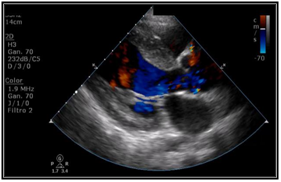

Transthoracic echocardiogram was performed in which trivalva aortic valve was observed with limited coaptation of the cusps that produces severe regurgitation, vena contracta of 6 mm, EROA of 0.5 cm2, aortic root of 36 mm, ascending aorta 35 mm, LVED 51mm, LVEF 59%. (Figure 2 & Figure 3) Severe aortic regurgitation was diagnosed, with Takayasu arteritis as probable etiology. Thoracic angiotomography and angiography were performed, showing areas of stenosis in the left carotid and the left subclavian artery. (Figure 4–7) The final diagnosis was severe aortic insufficiency secondary to dilation of the aortic root due to Takayasu's arteritis by Ishikawa criteria. Treatment with aortic valve replacement with mechanical prosthesis was decided.